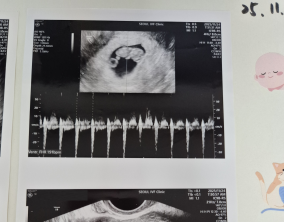

이유정 원장님을 믿고 걸어간 길 끝에서 만난 생명

이유정 원장님은 매 순간 환자의 마음을 읽어주시는 분이었어요. 부담 없이, 그러나 가장 효과적인 방향으로 치료를 이끌어주셨고, 그 덕분에 PGT-A에서 무려 5개의 통과 배아를 얻…

믿음으로 버틴 1년, 결국 다시 찾아온 아이

이경훈 원장님을 비롯해 원무 팀장님, 간호사 선생님들까지 모두가 정말 한결같이 친절하고 따뜻하게 맞아주셨어요. 우울할 수밖에 없는 시기였는데, 병원에서 받는 그 온기 덕분…